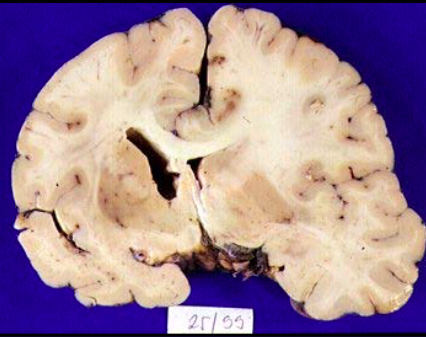

What occurs in prion disease?

PrPSC aggregates leading to neuronal death and holes in grey matter